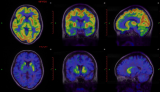

细数PET检查中的相同与不同

PET-CT/PET-MRI是目前临床广泛使用的高端影像检查技术,一次检查可以获得全身或局部的功能及结构信息,实现疾病早发现、早诊断、早治疗,显著改善预后;还可评估治疗效果和探测复发转移,在肿瘤、神经退行性疾病、心脑血管疾病的诊治中发挥着重要的作用。 2021-11-19 核医学PET/CTPET/MRI